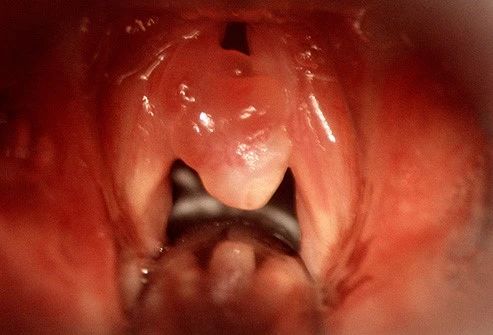

05 声带息肉

这是你声带覆盖物上的非癌性生长或病变。

声带息肉通常只生长在声带的一侧。你的声音可能会嘶哑、低沉,或者说不了一句完整的句子。说话或唱歌可能需要更多的努力或力量。

声带息肉的诊断和治疗:

你的医生会想知道你声音问题的全部历史。他们可能会用一根管子穿过你的嘴来检查你的声带。他们会检查胃酸反流、过敏和激素问题,这些都会让你的声音问题变得更糟。

少说话和特殊的发声练习可能是你康复所需要的。这部分取决于你如何使用你的声音。职业歌手可能需要做手术。